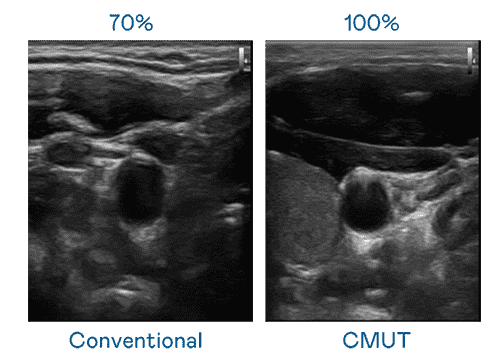

CMUT 技术是一种用电容式微机电元件来产生超音波讯号的技术。。。与传统 PZT 压电式技术相比,,,CMUT 频宽增加 30%,,,更宽频的超音波讯号让影像解析度大幅提升,,,是实现高影像品质医疗超音波扫描、、、促进精准医疗发展的关键技术。。

大频宽带来超清晰影像

超音波影像的解析度高低,,,,首先取决于探头能发出的讯号频宽。。壹号平台 CMUT 可提供高清晰的超音波讯号,,,提供高频宽、、、高灵敏度、、、影像纹理细节更高的超音波影像,,,协助医护人员缩短影像判读时间及利用精准的医疗影像进行诊断。。